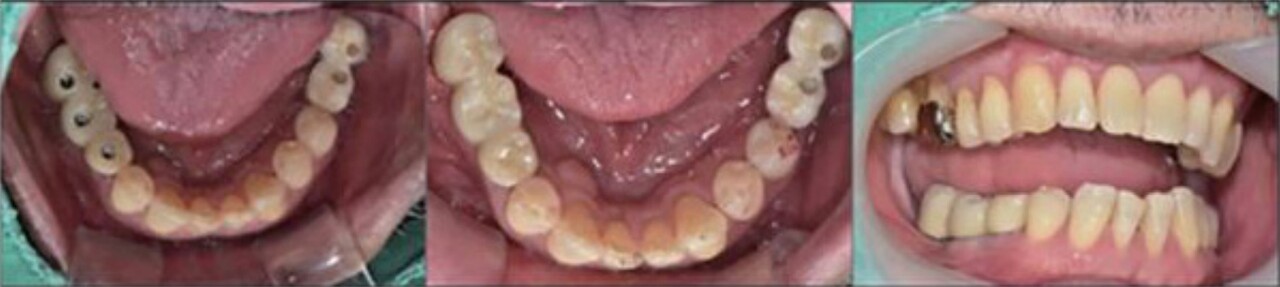

임플란트 custom abutment와 최종 보철물을 장착해주는 술식은 1) 임플란트 fixture에 abutment positioning zig를 이용하여 연결한 뒤에 Crown을 끼운 후에 abutment를 8분 간격 으로 2번 tightening 하고, 2) 보철물을 cementation 후에, 3) flowable resin으로 screw hole을 채워 준다(그림 19). 그 이후 중요한 과정으로 교합관계를 다시 한번 점검할 것을 추천한다.

Custom abutment and Zirconia prostheses delivery

Esthetic Restoration